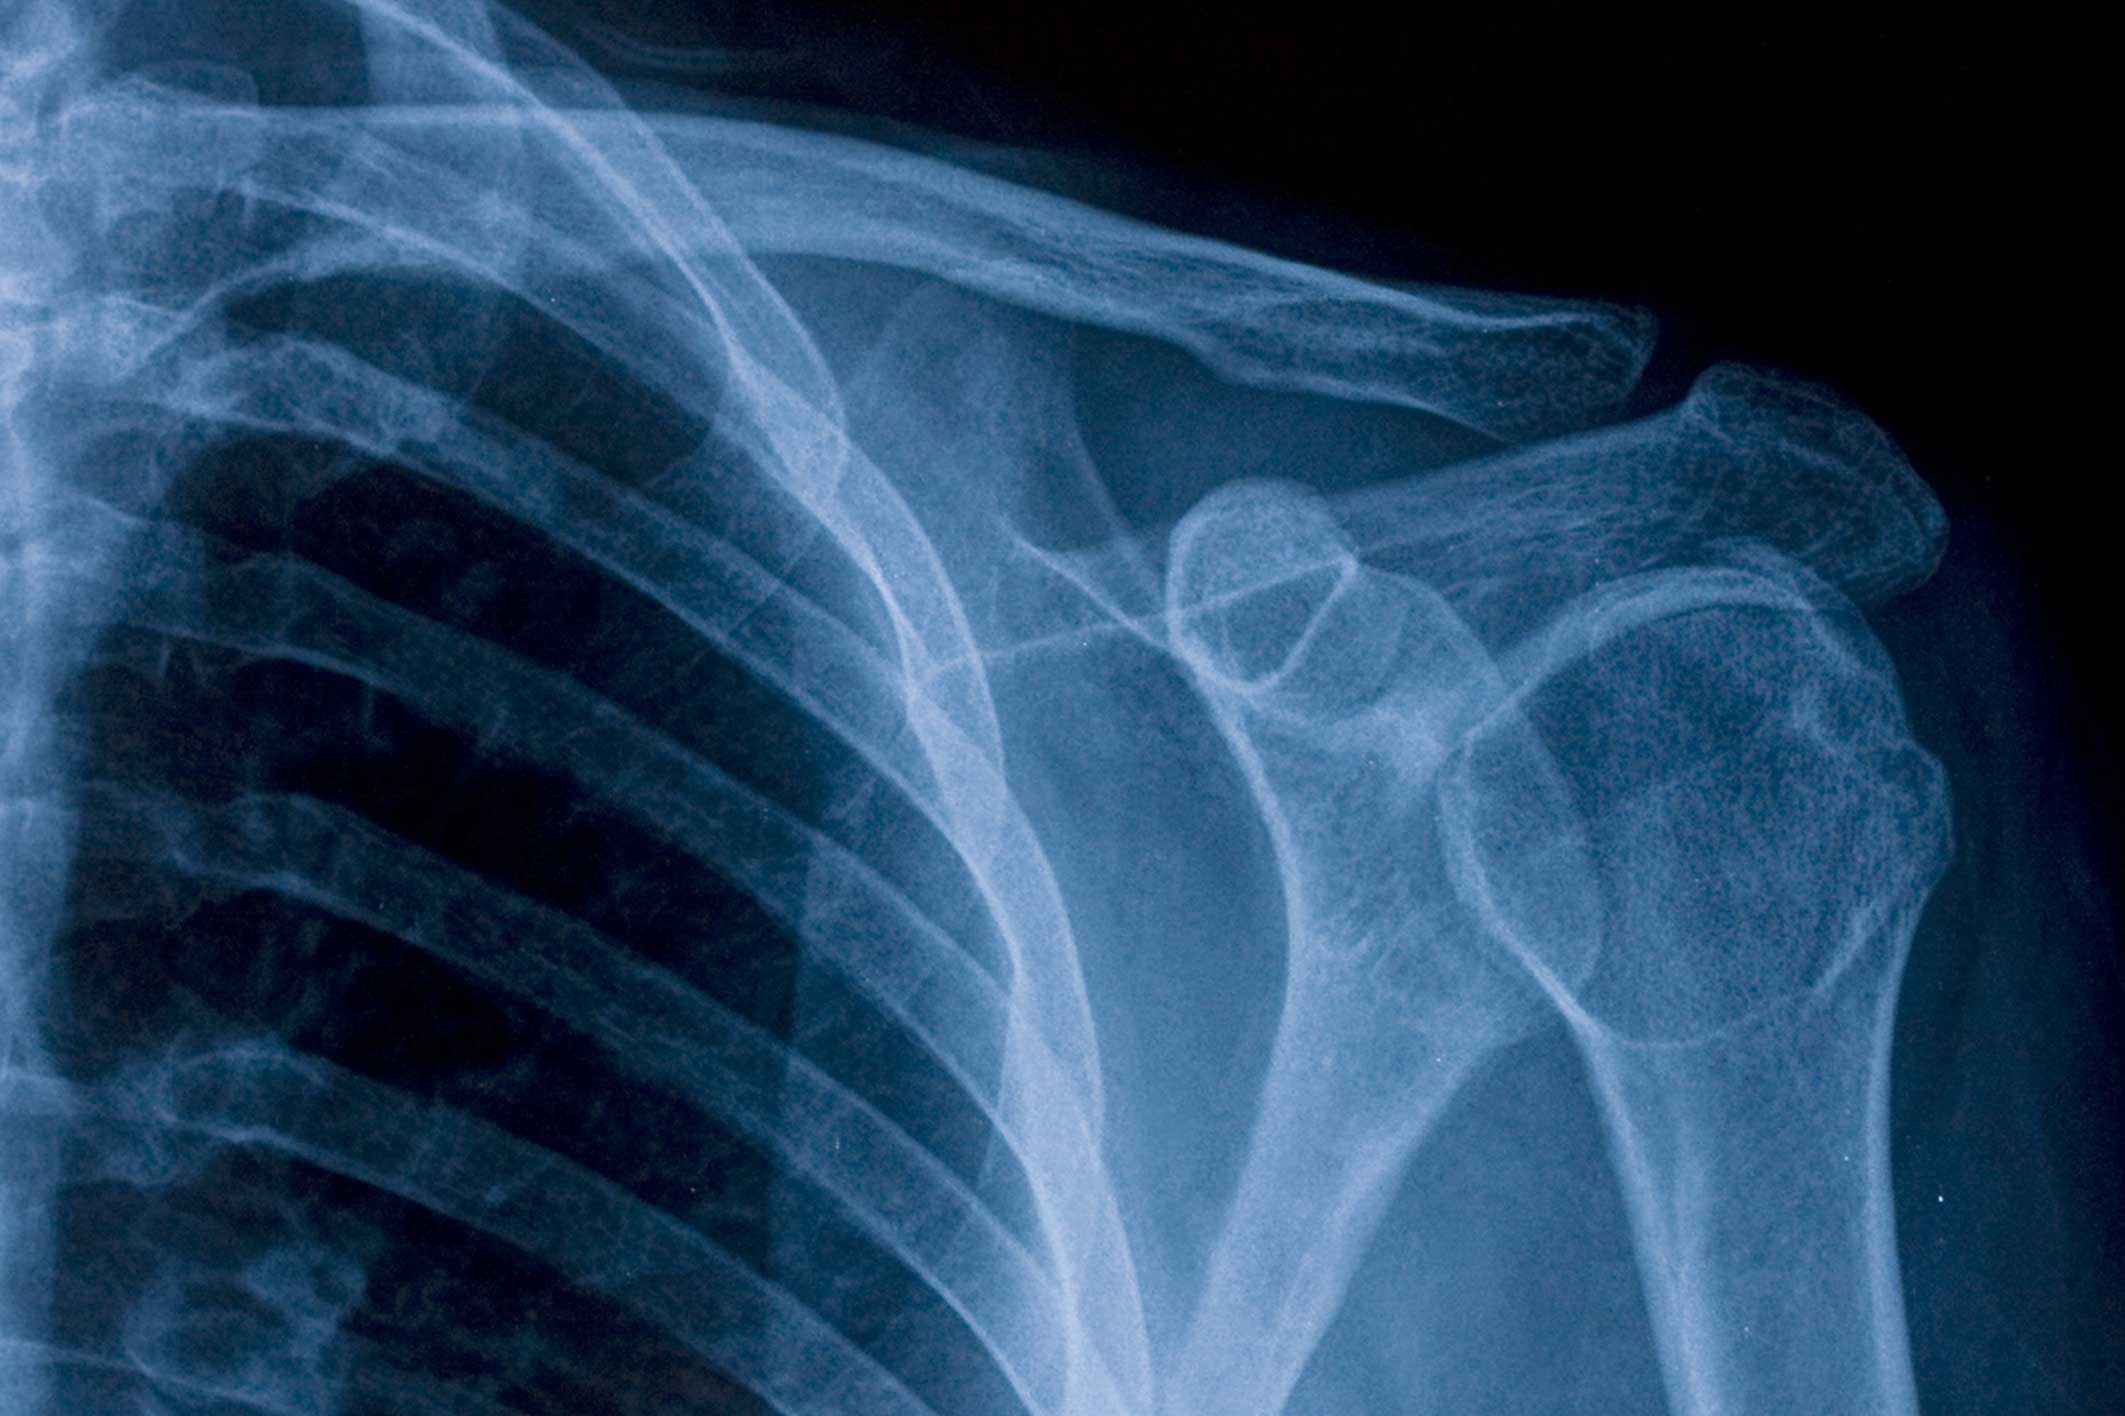

Shoulder Pain X-Ray Showed Nothing . you may feel pain only when you move your shoulder, or all the time. a variety of radiographic views have been described in the literature for the initial imaging of nonacute shoulder pain. shoulder radiographs are often the only imaging exam necessary for the evaluation of acute shoulder trauma, calcific. This article explains some of the common causes of shoulder The pain may be temporary, or it may continue and require medical diagnosis and treatment. shoulder pain is a common musculoskeletal complaint that may be due either to intrinsic disorders of the shoulder or.

a variety of radiographic views have been described in the literature for the initial imaging of nonacute shoulder pain. you may feel pain only when you move your shoulder, or all the time. This article explains some of the common causes of shoulder shoulder radiographs are often the only imaging exam necessary for the evaluation of acute shoulder trauma, calcific. The pain may be temporary, or it may continue and require medical diagnosis and treatment. shoulder pain is a common musculoskeletal complaint that may be due either to intrinsic disorders of the shoulder or.

Shoulder Pain X-Ray Showed Nothing you may feel pain only when you move your shoulder, or all the time. shoulder radiographs are often the only imaging exam necessary for the evaluation of acute shoulder trauma, calcific. shoulder pain is a common musculoskeletal complaint that may be due either to intrinsic disorders of the shoulder or. The pain may be temporary, or it may continue and require medical diagnosis and treatment. a variety of radiographic views have been described in the literature for the initial imaging of nonacute shoulder pain. you may feel pain only when you move your shoulder, or all the time. This article explains some of the common causes of shoulder